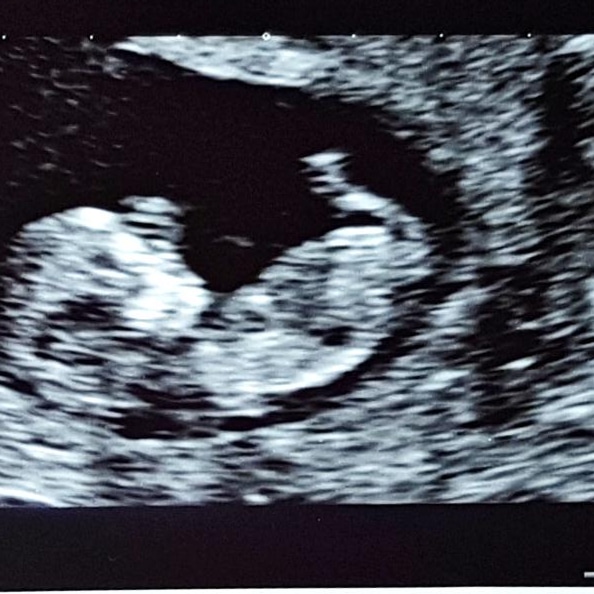

Baby is all good!!! Snoopster continues to be incredibly wiggly causing the trainee sonographer no end of problems in trying to do measurements… in fact the other sonographer ended up doing an estimation because little one wouldn’t stay still!! Heartbeat nice and strong. Feeling very relieved.